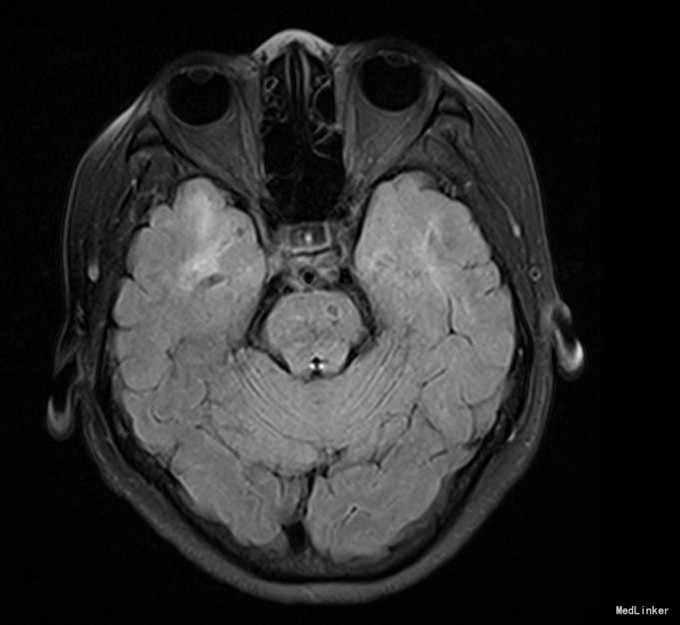

神清,说话吐词清晰。双侧瞳孔等大等圆,眼球运动正常,光反射灵敏,无面舌瘫,颈软。左手握力下降,右下肢轻瘫试验阳性,双上肢腱反射稍高,双侧膝反射亢进,霍夫曼征及内罗里索征阳性。直线行走试验阳性,闭目难立征阴性,双侧指鼻试验阴性。双侧病理征未引出,四肢浅感觉等称。实验室检查未见明显异常。MRI示:脑干、双侧颞极、外囊、额顶叶、放射冠区及丘脑、脑桥异常信号,结合MRS提示符合缺血性改变,部分软化灶形成.结合病变位置(颞极、外囊)及患者年龄,考虑CADASIL可能。头颈血管大致正常,NOTCH3基因见图